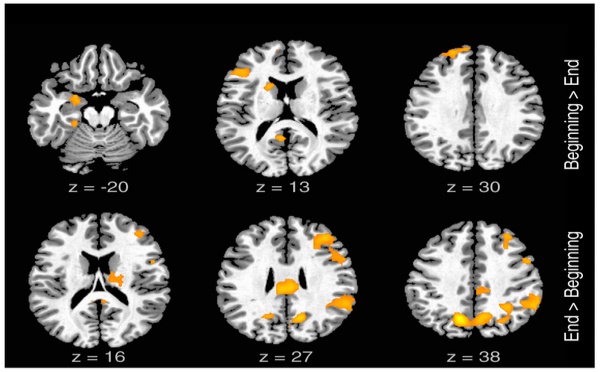

Definen la red neuronal que posibilita la improvisación lírica - 16/11/2012

El análisis de la actividad neuronal de cantantes de rap mientras estos improvisaban las letras de sus canciones ha revelado que el cerebro utiliza una red neuronal específica en las improvisaciones líricas. Dicha red estaría relacionada con la motivación, el lenguaje, el humor y la acción. El estudio arroja nuevas claves sobre la capacidad creativa de nuestra especie y su correlato cerebral.